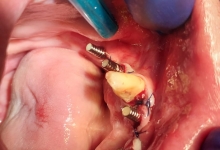

IMPLANTOLOGIE

SUPRAPROTEZAREA PE IMPLANT